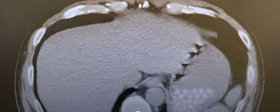

คุณหมอเล่าว่า เมื่อสัปดาห์ที่ผ่านมา เพิ่งทำการ X-Ray ช่องท้องของผู้ป่วยชายรายหนึ่ง ก่อนที่คุณหมอจะพบสิ่งผิดปกติในช่องท้อง กระเพาะอาหาร ลักษณะเป็นจุดสีขาวโปร่งแสง มากกว่า 20 จุด กระจุกรวมอยู่ทั่วช่องท้อง และไม่รู้ว่าคืออะไร

ในตอนแรกคุณหมอกังวลว่าอาจจะเป็นสัญญาณของโรค จนเรียกคนไข้เข้ามาซักประวัติอีกที กลับกลายเป็นเรื่องสุดฮา เพราะคนไข้บอกกับคุณหมอว่า เพิ่งรับประทานชานมไข่มุก โดยกลืนไข่มุกลงไปทั้งลูกไม่ได้เคี้ยว กลับกลายเป็นว่าจุดสีขาวที่พบในฟิล์ม X-Ray นั้น แท้จริงก็คือไข่มุกนั่นเอง